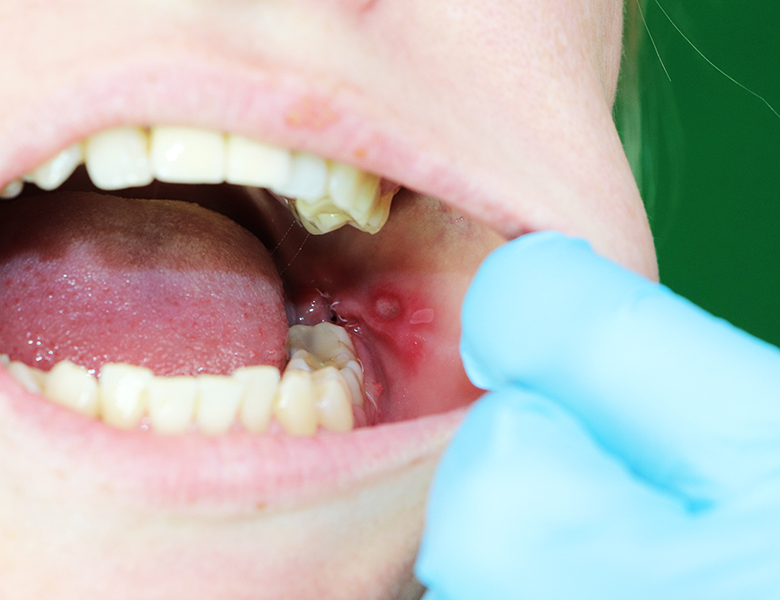

唇や舌の下のぷっくりとした袋(粘液嚢胞)

下唇の裏や舌の裏にできる、直径数ミリ〜1センチ程度の透明、あるいは青紫色の柔らかい膨らみです。

唾液を作る小さな工場(小唾液腺)の出口が、誤って噛んでしまったりすることで詰まり、唾液が組織の中に漏れ出して袋状に溜まったものです。

潰れると一時的に小さくなりますが、数日で再発を繰り返すのが特徴です。

当院の対応

自然に治ることもありますが、再発を繰り返す場合は原因となっている唾液腺を含めた摘出が必要になるため、適切な医療機関をご紹介します。